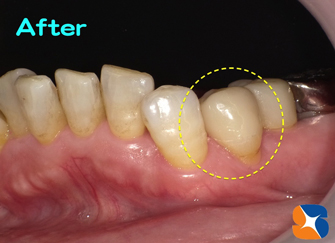

最後に、Dr.が色の手直しとツヤ出しを行えば完成です。

午前中に来院。お昼休みを使って午後には完成しました。

午前中に来院。お昼休みを使って午後には完成しました。

※当院では、他人に依頼することなく、私が責任をもって一から十まで製作しますので、完璧な仕上がりであると自負しています。

オールセラミックの被せ物が長持ちするか否かは、ほぼ100% Dr.の技量に左右されます。自分の削り方を過信することなく、PC内で100倍に拡大して歯をチェックすれば、おのずと治療レベルは数段 向上します。

オールセラミックの被せ物が長持ちするか否かは、ほぼ100% Dr.の技量に左右されます。自分の削り方を過信することなく、PC内で100倍に拡大して歯をチェックすれば、おのずと治療レベルは数段 向上します。